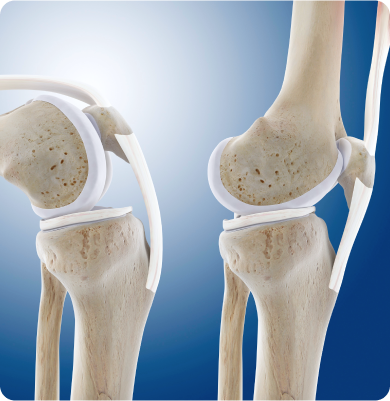

무릎 질환 수술적 치료 방법

인공관절수술(전치환술, 부분치환술, 재치환술), 관절내시경 수술(미세천공술,연골성형술,자가골연골 이식술), 교정절골술, 반월상 연골판 절제술/봉합술, 인대재건술

무릎 질환 비수술적 치료 방법

골수 흡인 농축물 관절강내 주사(BMAC), PRP 관절강내 주사, 관절강내 연골주사치료, 물리치료